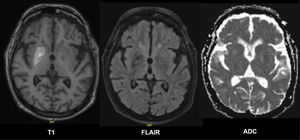

Se realizó una resonancia magnética cerebral (RMC) bajo sedación debido a su inquietud motora. La RMC mostró hiperintensidad en secuencia T1 del estriado, predominantemente en el putamen derecho, sin restricción en difusión, hallazgos compatibles con estriatopatía de origen metabólico (fig. 1).

Hiperintensidad en secuencia T1 del estriado, predominantemente en el putamen derecho. Secuencia fluid attenuated inversion recovery (FLAIR) con hipointensidad en putamen derecho. Coeficiente de difusión aparente (ADC) sin evidencia de restricción a la difusión. Hallazgos compatibles con estriatopatía diabética.